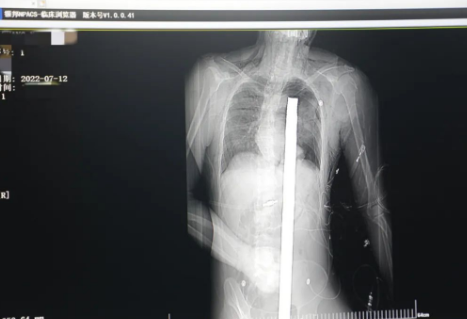

突發(fā)!太疼了,1.2米長的螺紋鋼從男子會陰部垂直穿入胸腔......7月12日下午16時10分,西安一處工地的一名26歲工友,不慎從10多米的高空墜落,不幸的是工地上一根直徑3厘米的螺紋鋼從男子會陰部垂直穿入體內(nèi),工地上的工友們小心翼翼地將連著的鋼筋截斷。情況危急,立即送往西安國際醫(yī)學中心醫(yī)院急救中心,此時正是下午17時00分。

時間就是生命!此時,西安國際醫(yī)學中心醫(yī)院展開了一場與生命賽跑的搶救,第一時間開辟綠色通道,急診X光片及CT顯示:異物經(jīng)會陰部貫穿盆腔、腹腔到達左側胸腔主動脈弓水平。醫(yī)院創(chuàng)傷中心立即啟動應急預案,劉延彤副院長親臨指揮,下午17點48分,當患者被送達手術室,胸外、心外、肝膽外科、胃腸外科,泌尿外科及麻醉科等多學科專家聯(lián)手對這名工友進行“縱劈胸骨 前外側開胸探查 氣管及主支氣管修補 肺修補 血胸清除 開腹探查止血 腹膜后及盆腔探查......”手術。

情況緊急!術中探查后發(fā)現(xiàn),長120cm直徑3cm的螺紋鋼經(jīng)患者右側會陰部穿入,傷及直腸,途徑膀胱后方,左側髂總動靜脈之間傷及左腎后,經(jīng)胰腺后方在肝脾之間穿破膈肌,在下肺靜脈前方穿入左肺穿破氣管及左右主支氣管膜部,止于主動脈弓下水平,穿入體內(nèi)的部分達到75cm。